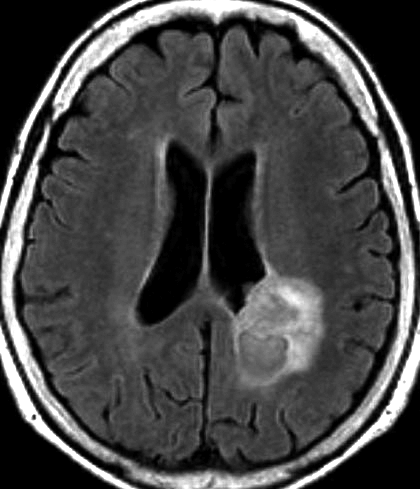

- MRIでは大脳表面にあり,のう胞(液体の溜まっている袋)と腫瘍の塊があります

- 大脳にくっついているのですが,大脳の中には育たないで,大脳からキノコのように生えてこともあります

- 大脳表面ののう胞を伴う限局性の腫瘍で,原則的にはくも膜下腫瘍ですが硬膜にも付着することが多いです

- 側頭葉表面に頻度が高いです,次いで前頭葉です

- 緩徐に増大します髄膜にくっつくので,のう胞性髄膜腫と誤診されることもあります

- 腫瘍周囲脳浮腫が目立たないものが多いです

- 他の腫瘍と区別できる特徴に乏しいので,多形黄色星細胞腫をMRIで診断することはできません